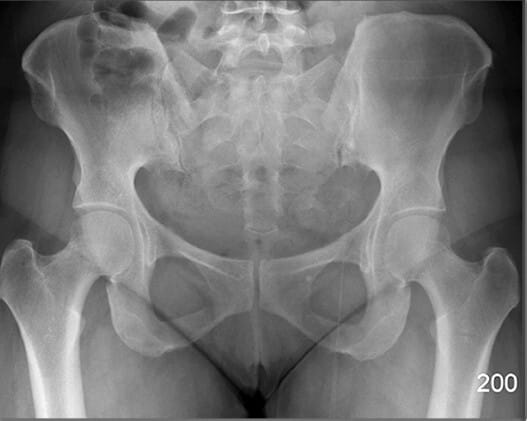

Bony Structures (AP View)

Pelvic Region

PELVIS

FEMUR